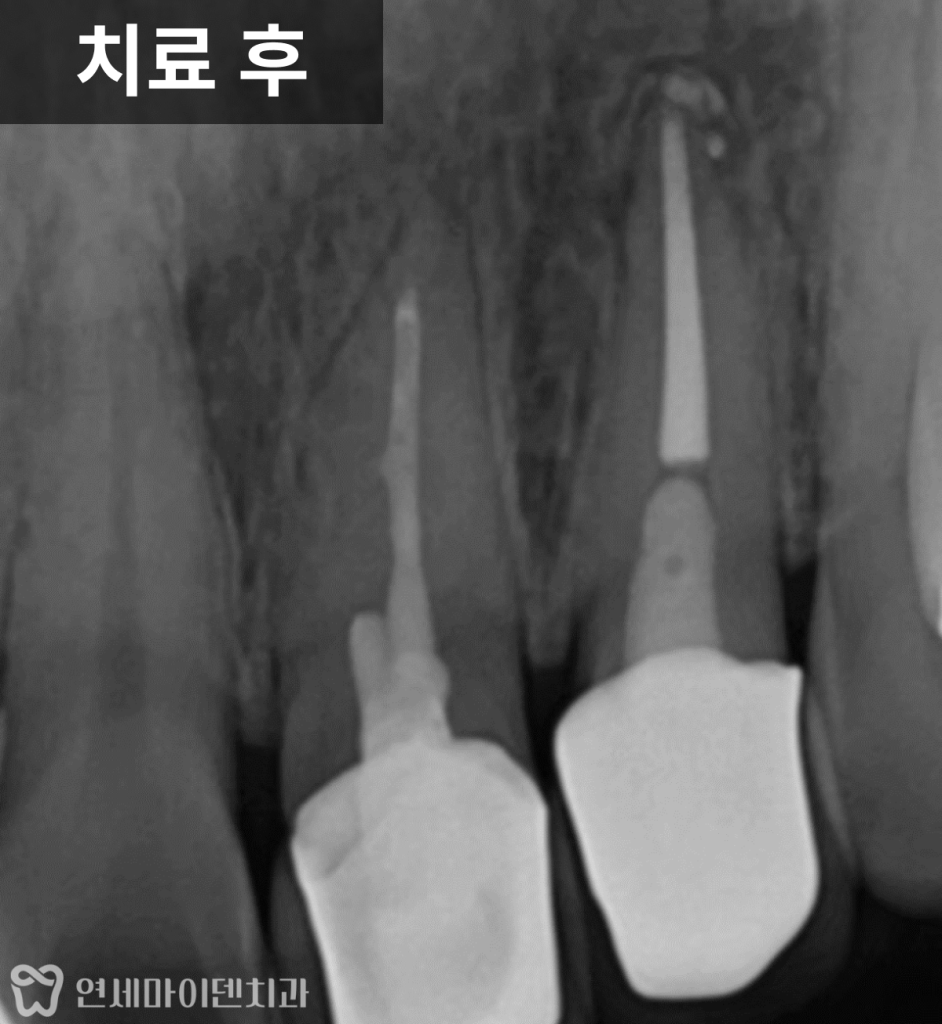

치료 후 6개월, 염증의 변화

재신경치료 후 약 6개월이 지나자

뿌리 끝에 있던 염증은 점차 줄어들고

뼈가 다시 차오르는 양상이 확인되었습니다.

결과적으로 치근단 절제술이나 발치 없이

재신경치료와 크라운만으로

치아를 보존

할 수 있었습니다.

수술까지 진행할 수 있었던 상황이었지만,

원칙적인 접근을 통해

보다 보존적인 방향으로 치료가 마무리된 케이스입니다.